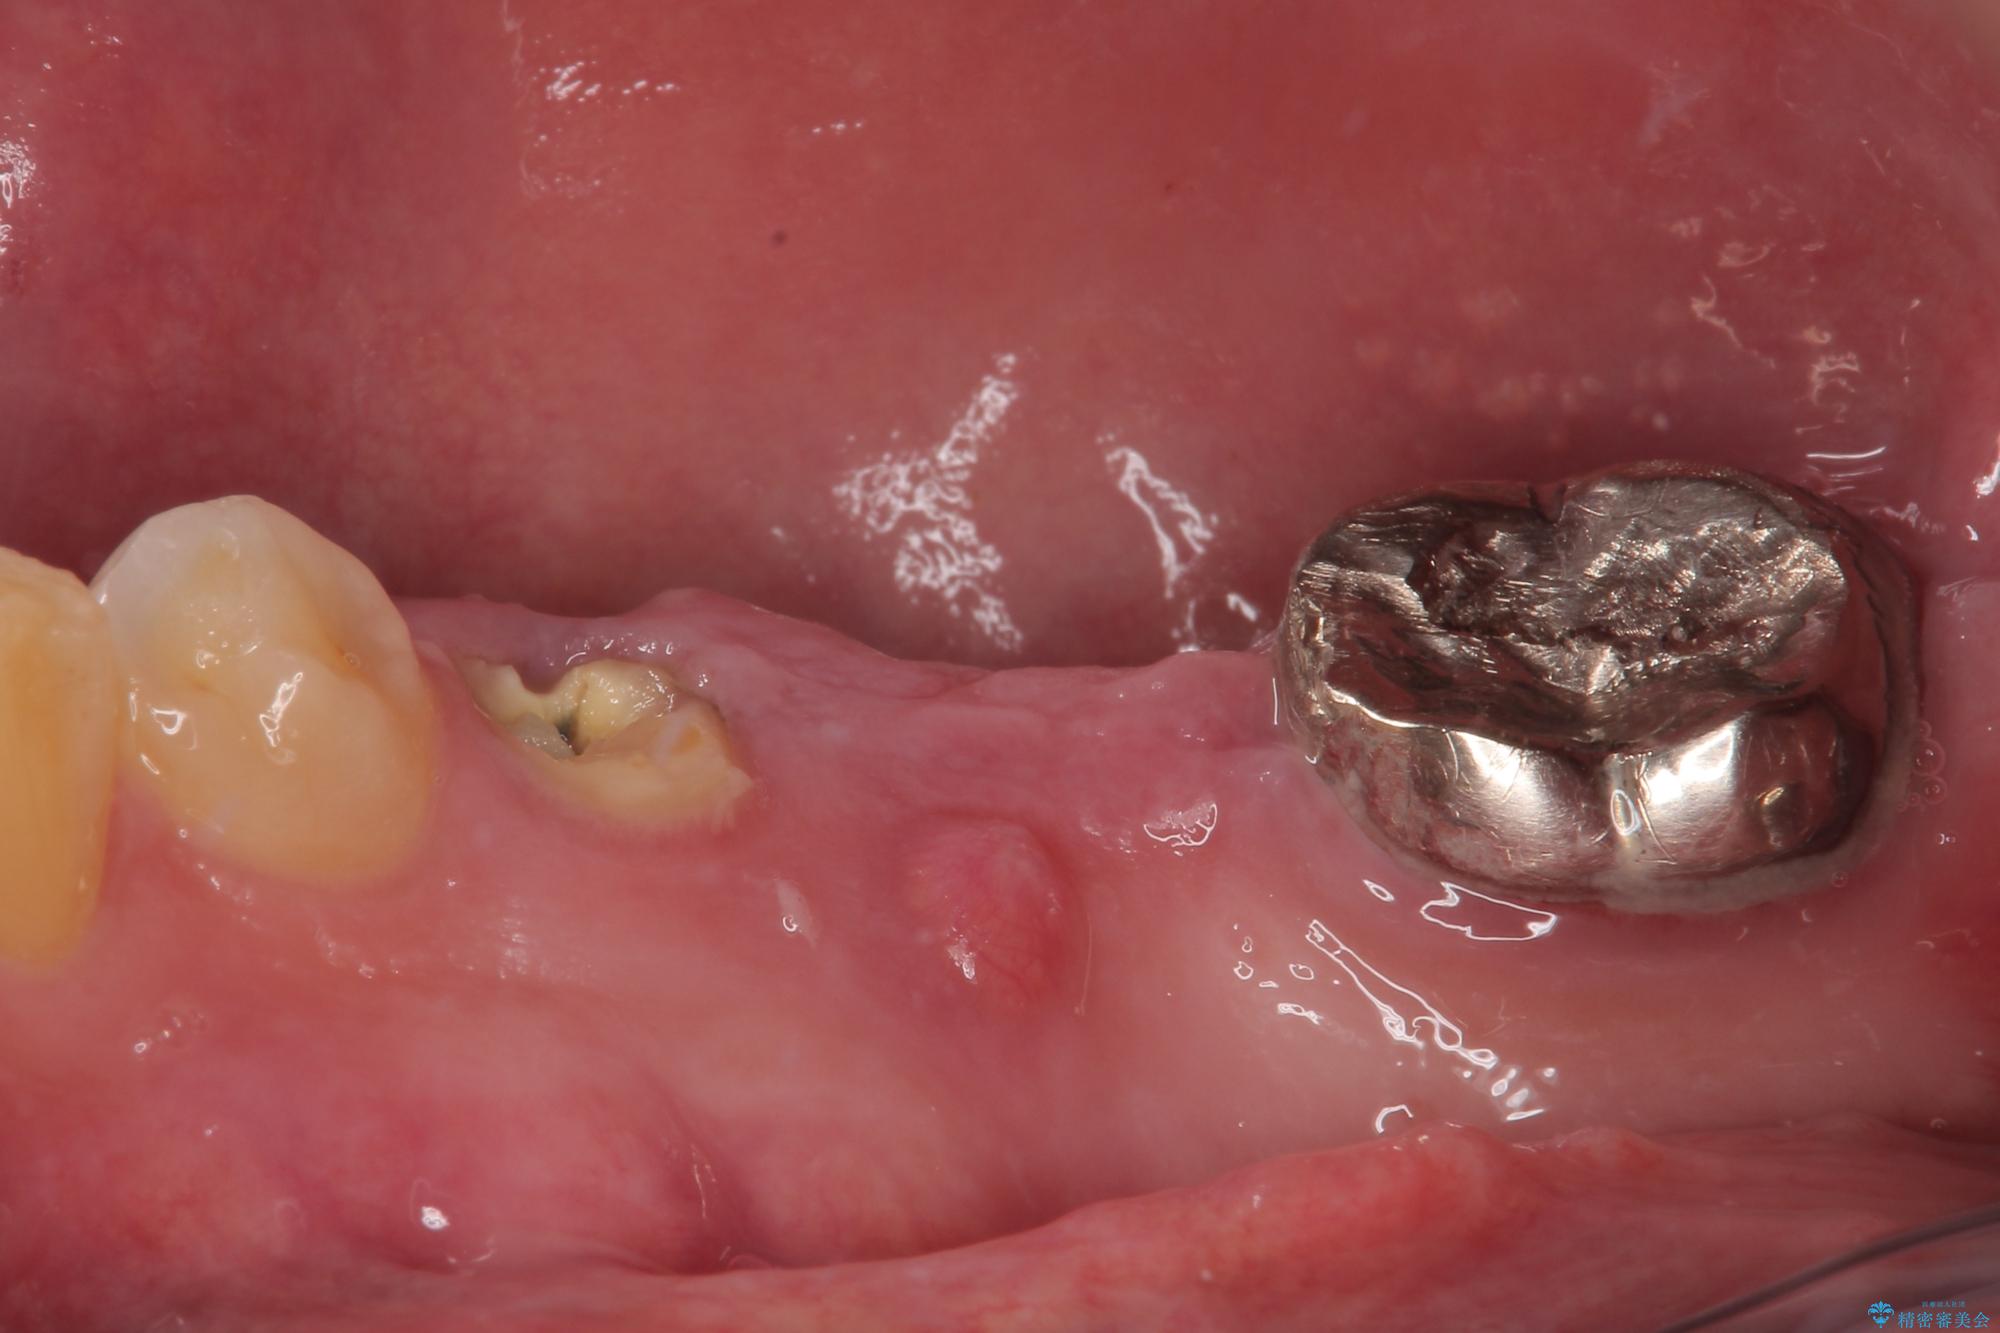

- むし歯を放置したことで、歯茎で膿が腫れ上がったしまったとのことで来院された患者様です。

ブリッジの支台歯が痛みを覚え、近医でブリッジを切断してもらって以降、そのままにしてしまったとのことでした。

問題が起きていた手前の歯から膿が出てきたことを自覚して当院を来院されましたが、既に歯根破折をしており、抜歯が必要な状態でした。